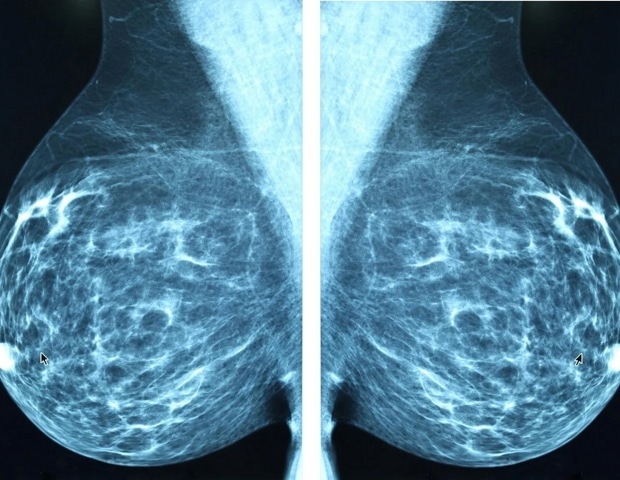

Η ABC Global Alliance παρουσίασε σήμερα την Έκθεση για τον Καρκίνο του Μαστού (ABC) για την περίοδο 2015-2025, μια σημαντική παγκόσμια αξιολόγηση που αποκαλύπτει μια δεκαετία εντυπωσιακής επιστημονικής προόδου. Αυτή η πρόοδος έχει μεταμορφώσει τη φροντίδα για τον καρκίνο του μαστού σε ορισμένες χώρες, αλλά πολλοί άλλοι ασθενείς σε διάφορες περιοχές του κόσμου παραμένουν χωρίς τα απαραίτητα οφέλη.

Η έκθεση αναδεικνύει τις βαθιές και επίμονες ανισότητες που αφήνουν πίσω πολλούς ασθενείς. Το κεντρικό θέμα της, «Γνώση σε Κίνηση», τονίζει την επείγουσα ανάγκη να μεταφραστεί μια δεκαετία αποδείξεων και καινοτομίας σε δράσεις που θα αλλάξουν τη ζωή κάθε ατόμου που ζει με καρκίνο του μαστού.

Η έκθεση επιβεβαιώνει ότι η συλλογική δράση της τελευταίας δεκαετίας έχει αποφέρει σημαντικές προόδους στη φροντίδα για τον καρκίνο του μαστού, αποδεικνύοντας ότι η πρόοδος είναι εφικτή. Ωστόσο, η άνιση κατανομή αυτής της προόδου έχει διευρύνει την απόσταση μεταξύ του εφικτού και της πραγματικότητας που βιώνουν οι περισσότεροι ασθενείς.